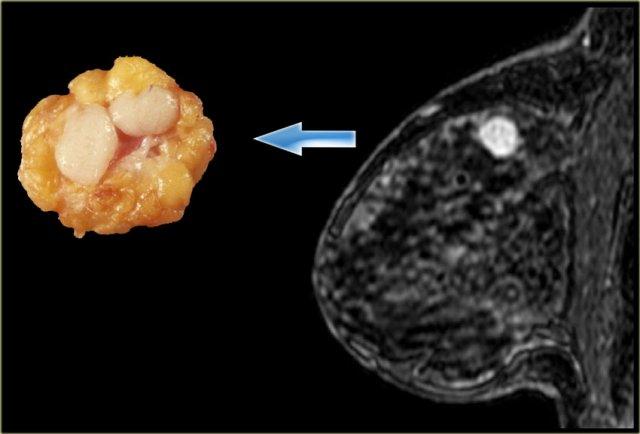

Ngoài cùng bên trái là một ví dụ khác về u xơ tuyến với các vách ngăn không ngấm thuốc rõ ràng.

Các vách ngăn này cũng có thể quan sát thấy trên tiêu bản đại thể bệnh lý.